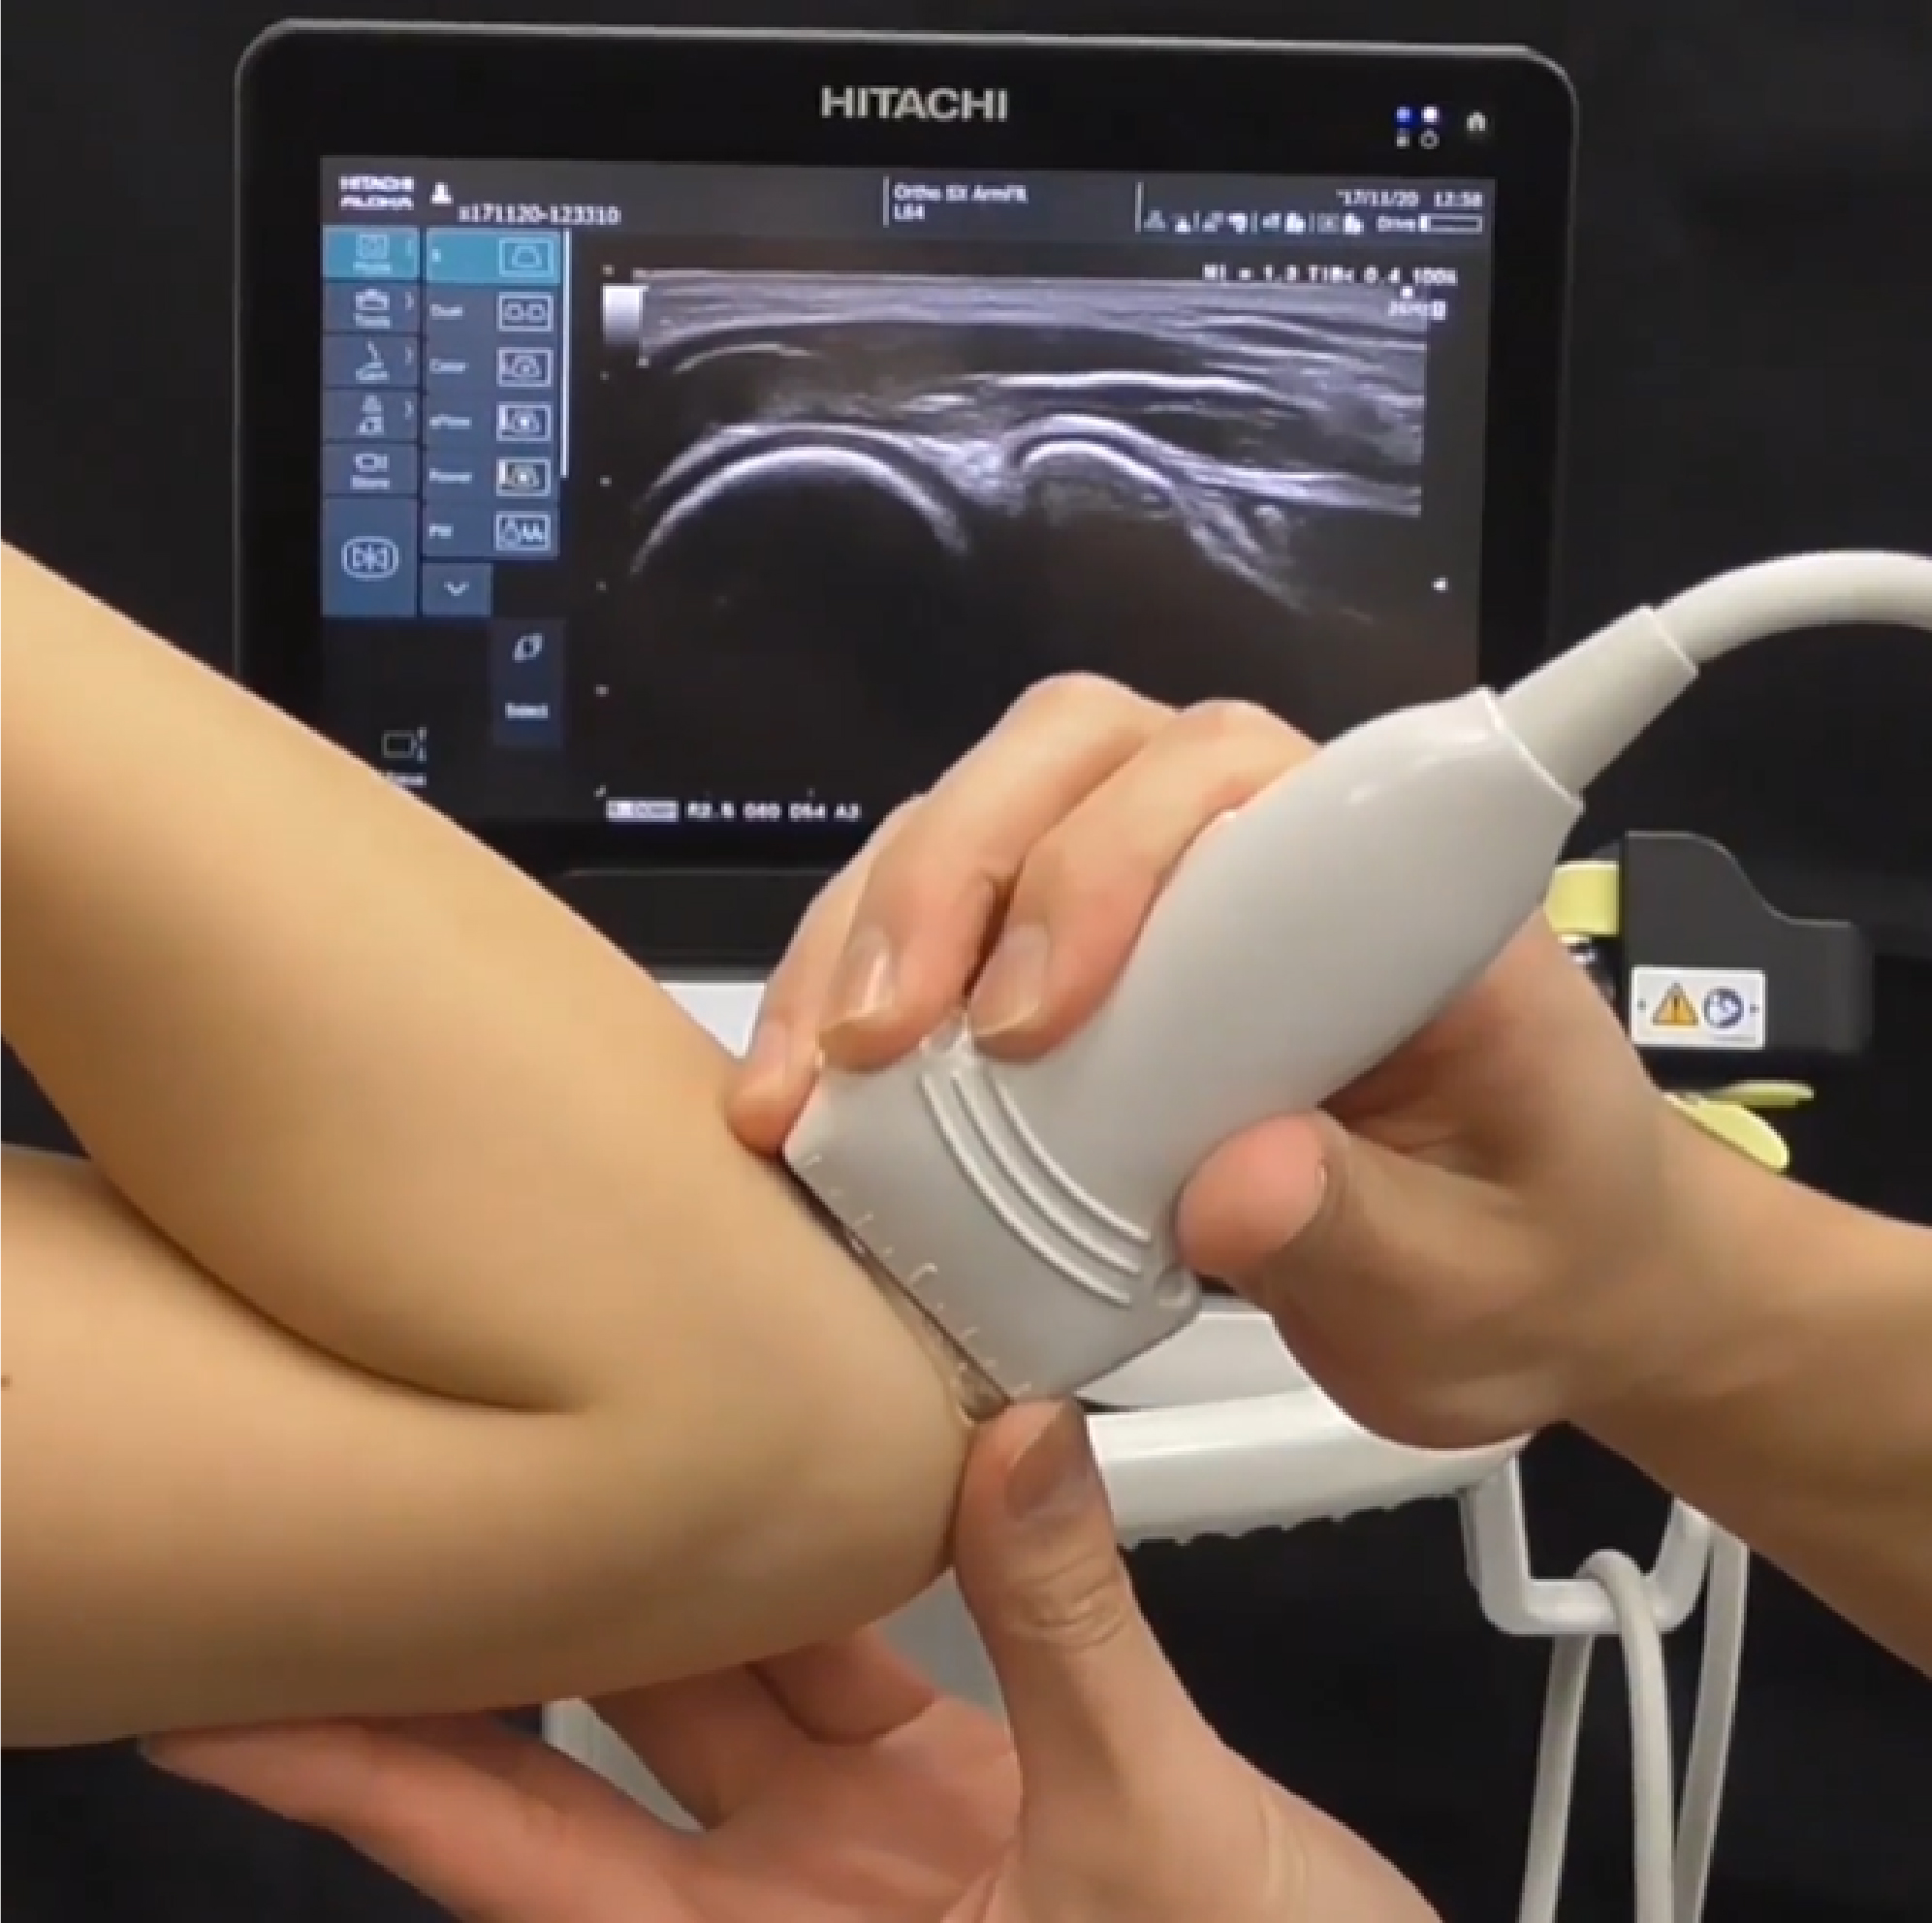

超音波診断装置(カラー)|日立製作所|超音波診断装置|ARIETTA

運動器の超音波-www.connectedremag.com